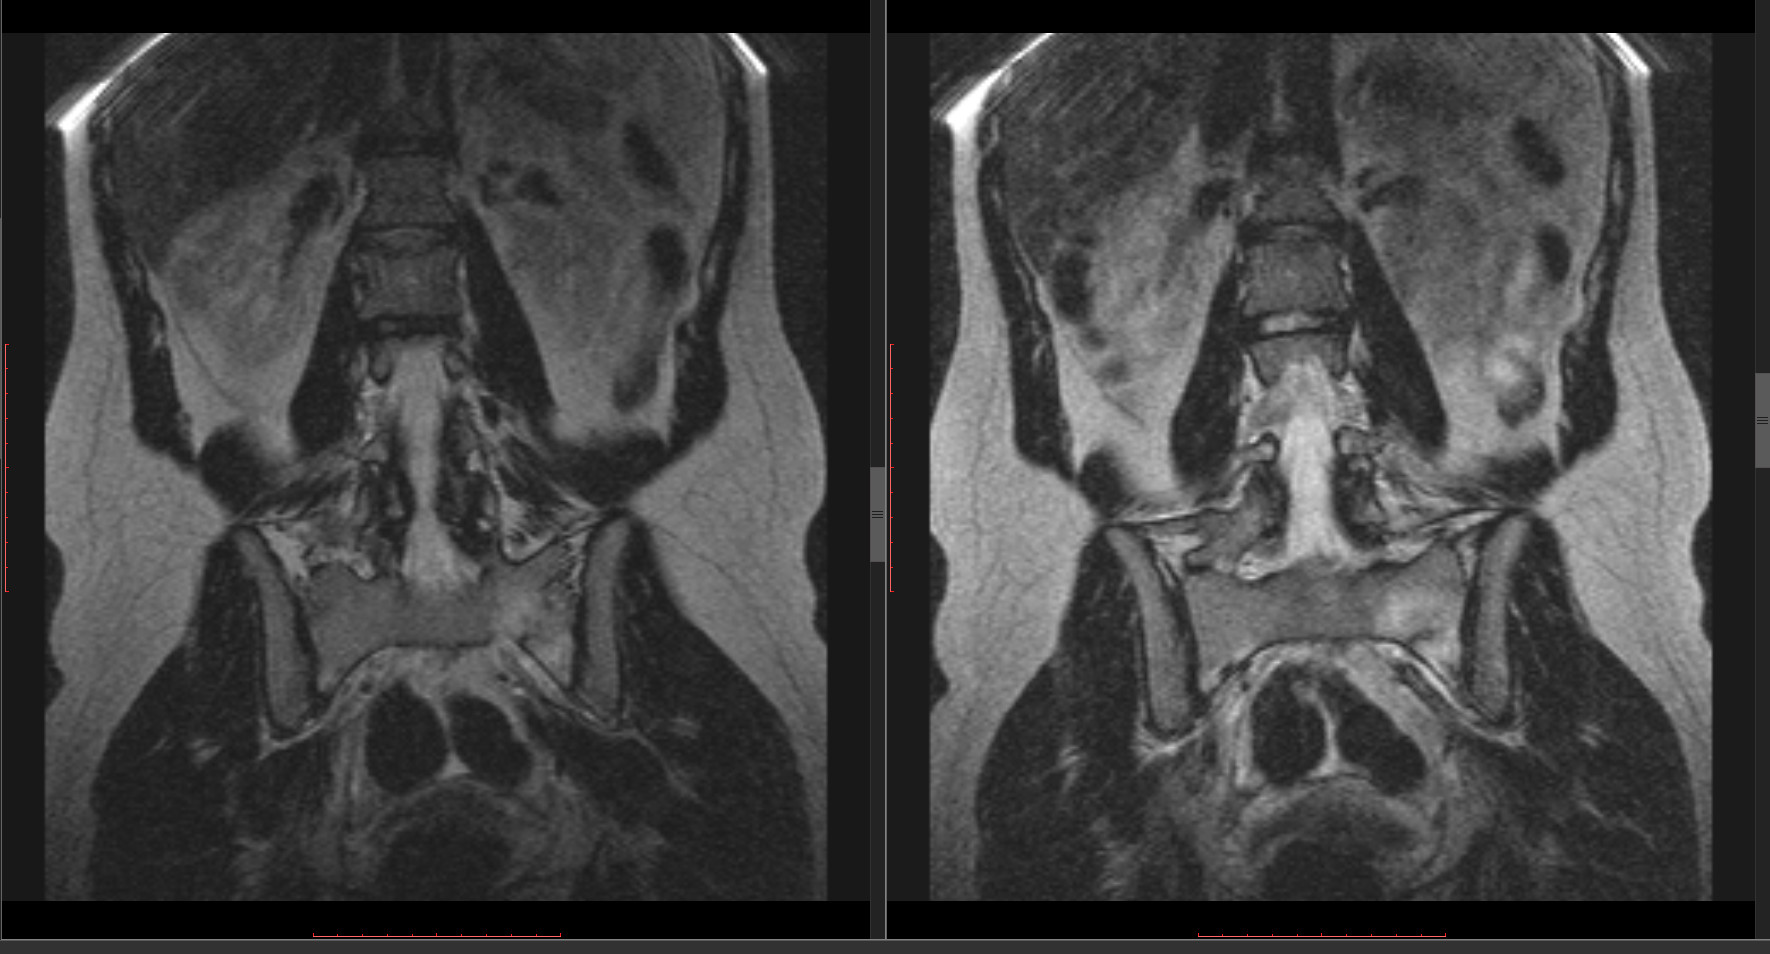

Это?

Приложения:

prezentaciya1.jpg

vadim losevichev wrote:

Видимо да, тут лучше видно